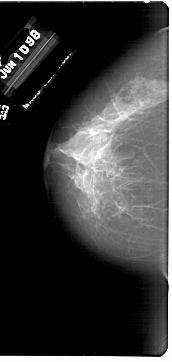

A_1847_1.RIGHT_MLO

FILE: A_1847_1.RIGHT_MLO.OVERLAY

TOTAL_ABNORMALITIES 1

ABNORMALITY 1

LESION_TYPE MASS SHAPE ARCHITECTURAL_DISTORTION MARGINS SPICULATED

ASSESSMENT 4

SUBTLETY 4

PATHOLOGY BENIGN

TOTAL_OUTLINES 1

BOUNDARY